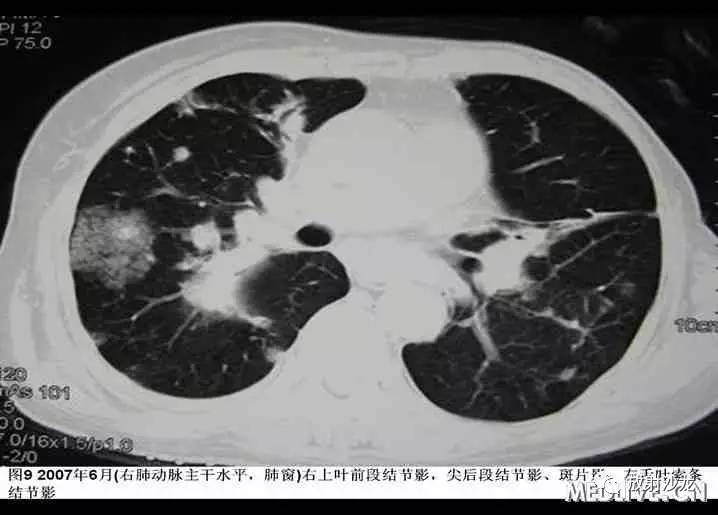

入院后患者最高体温在38℃左右,给予“拜复乐及大扶康”治疗后无显效,复查胸部CT提示肺内病变较2007年3月有加重(见图9-12),遂再次行CT引导下经皮肺穿。穿刺后患者最高体温维持在39℃左右,考虑感染不能完全除外,于2007年6月19日起加用稳可信0.5g Q8h及复达欣1.0g Q8h,6月21日加用口服大扶康200mg Qd,发热未见改善。结合两次肺穿及外院VATS的标本,病理科诊断“肺Castleman病(多中心型)(见图13)” 免疫组化:CD3(+)、CD20(+),AE1/AE3(+),CD21(+)”。6月21日转入血液科化疗,并于6月22日予CHOP方案化疗(CTX 600mg d1, 400mg d4, 西艾克4mg d1, 艾达生80mg d4, 强的松80mg d1-5)。化疗后未再发热,咳嗽、咳痰症状缓解,6月27日复查CXR示右下肺团块影较1月前吸收予以一疗程CHOP化疗后,患者体温正常,复查胸片提示右下肺阴影较前有明显吸收。后又间断予以CHOP方案化疗3程,2008年2月初,因受凉后发热,出现渐加重的气短,家属及患者放弃进一步诊疗,于2008年2月下旬去世。